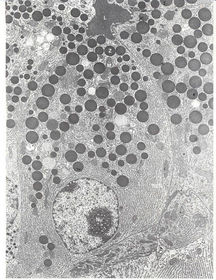

Enteroendocrine cell (Open type) A: Basal electron dense granules

Enteroendocrine cell (Closed type) A: basal electron dense granules